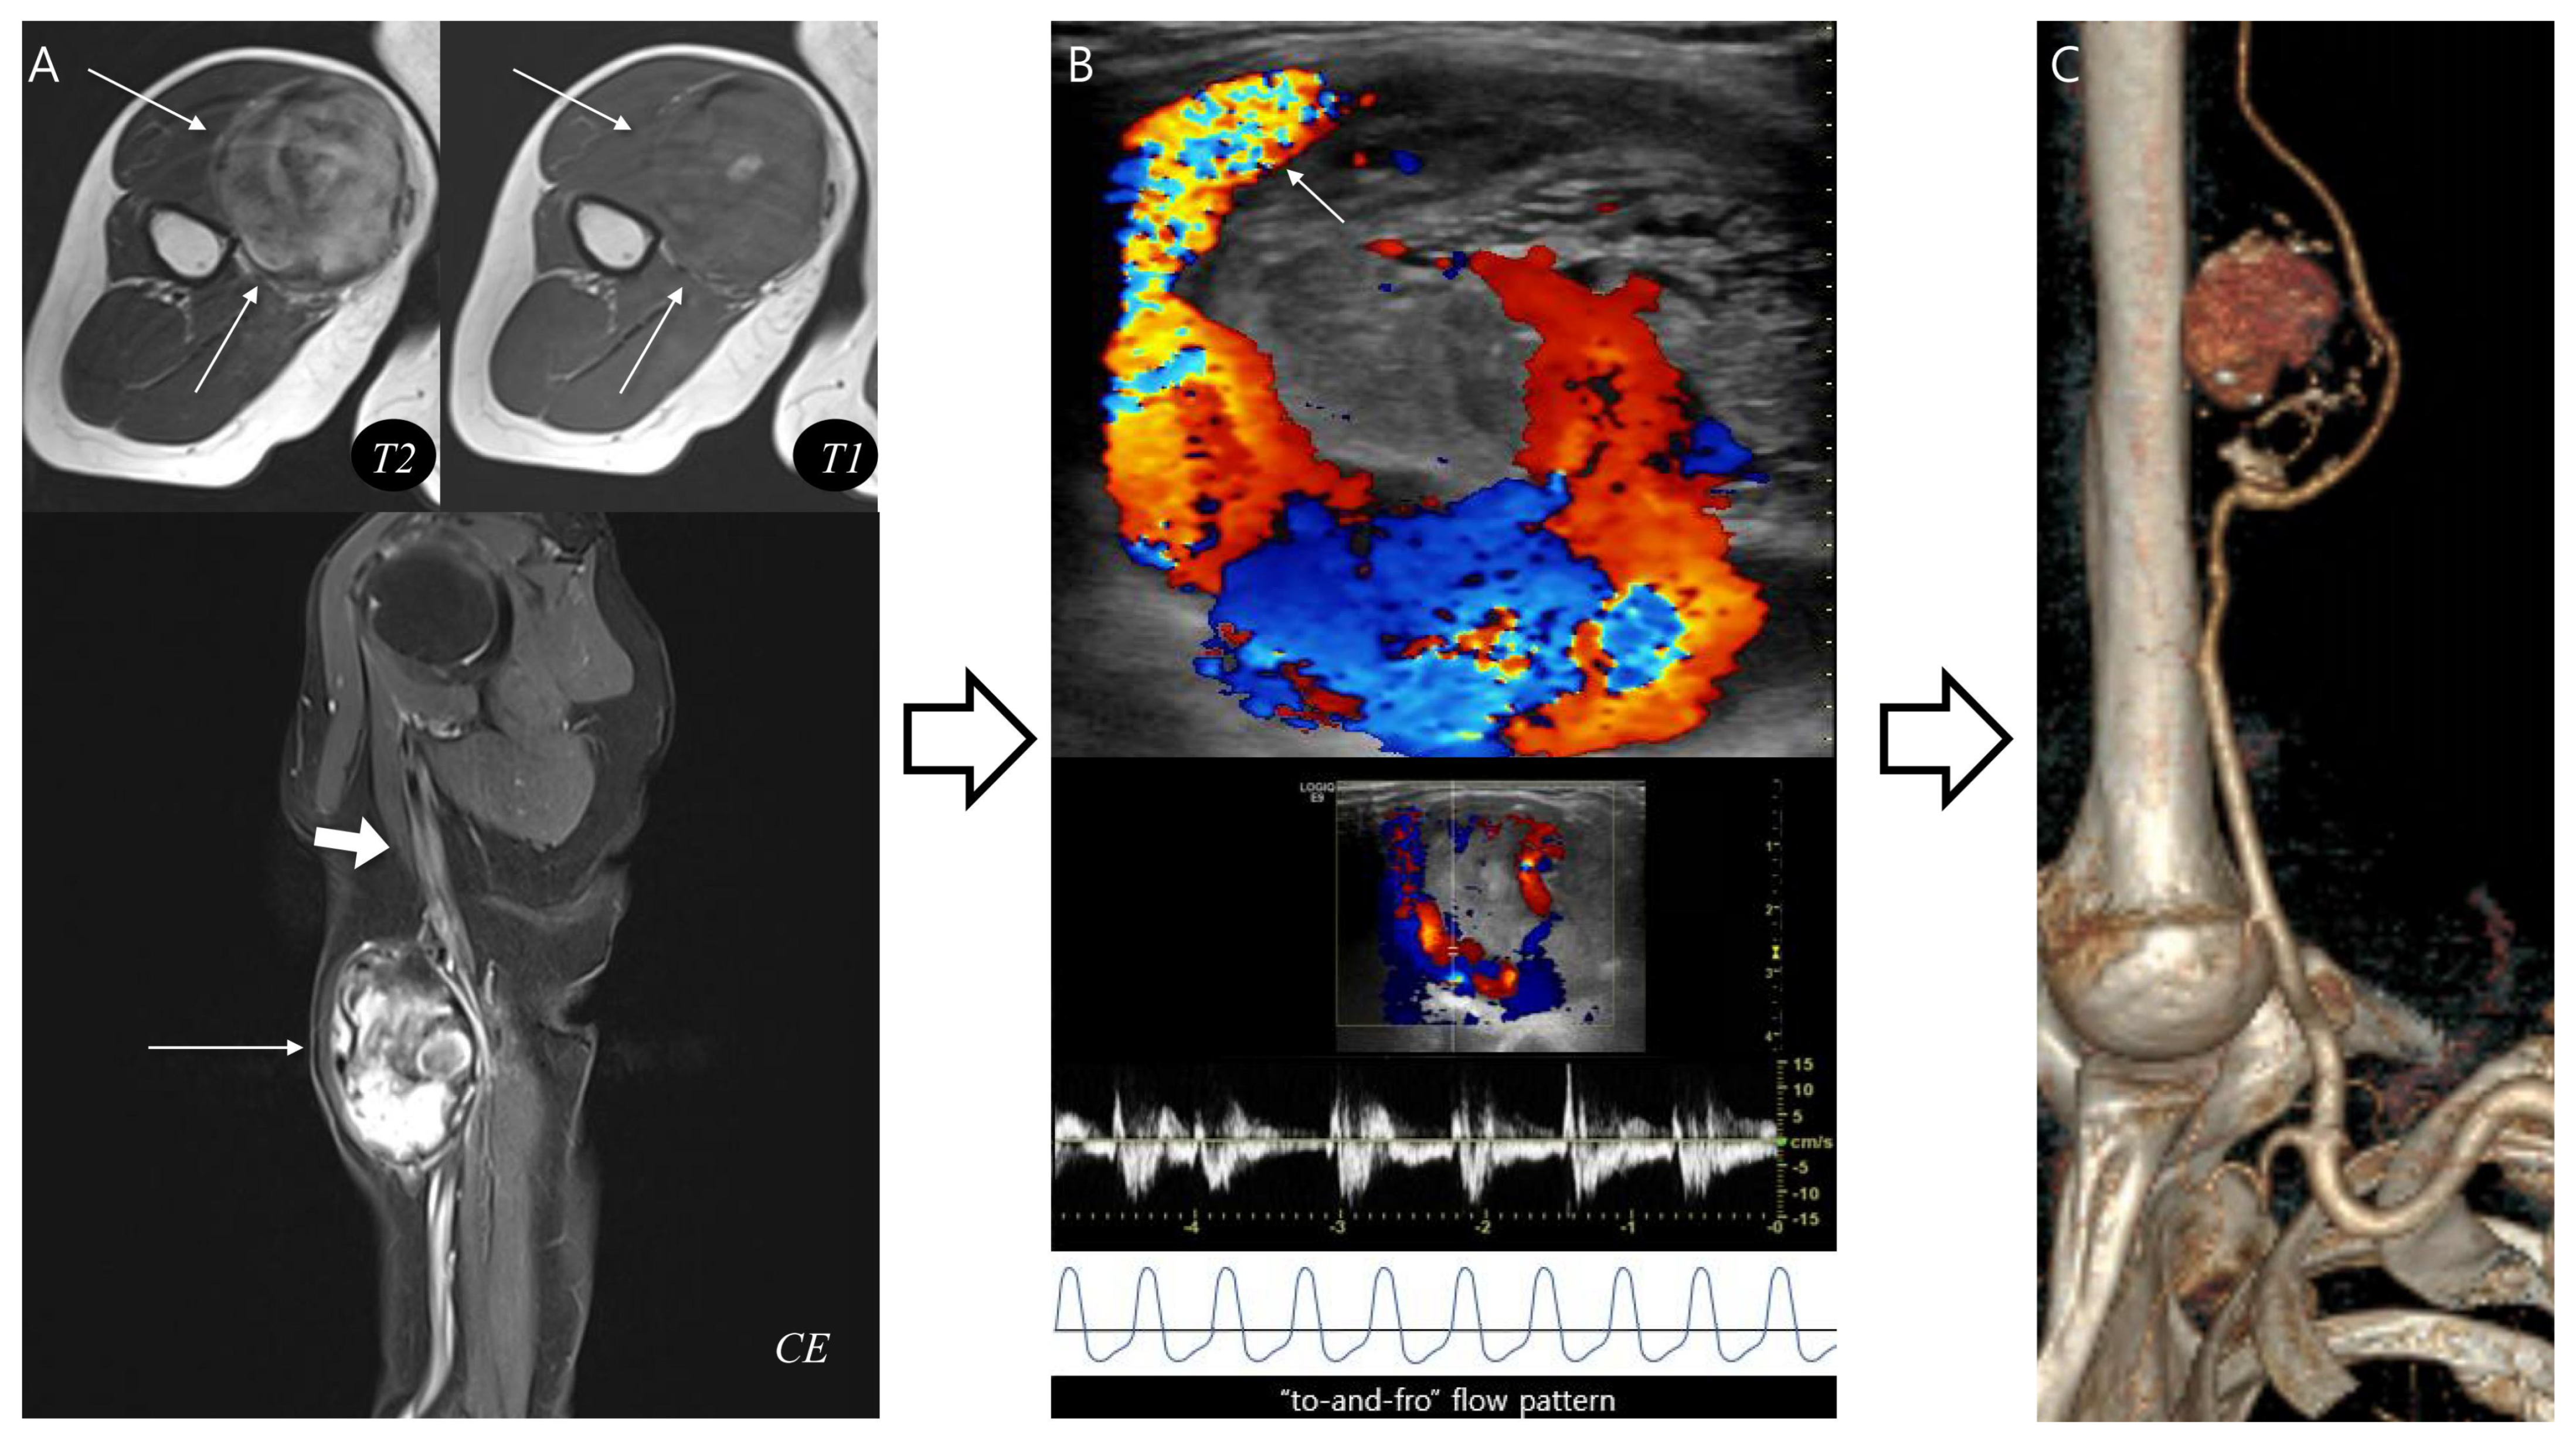

In the last pseudoaneurysm case (Figure 5), typical MRI findings, such as a central flow void was equivocal and inner peripheral high SI on T1WI was absent, making the diagnosis more challenging. Instead, the presence of neurovascular bundle involvement raised strong suspicion for pseudoaneurysm which was subsequently confirmed by complementary vascular imaging. This case demonstrates that the diagnostic flowchart retains its clinical value even in atypical presentations, underscoring the importance of integrating ancillary features such as neurovascular involvement to achieve accurate diagnosis and ensure appropriate treatment.

Figure 5.

Pseudoaneurysm with neurovascular bundle involvement diagnosed without biopsy. (A) Axial T2-weighted and T1-weighted MR images demonstrate a hematoma-like lesions (thin arrows) with equivocal central flow void or absent inner peripheral high SI. However, neurovascular bundle involvement (thick arrow) in sagittal T1-weighted contrast-enhanced MR image raises suspicion for pseudoaneurysm. (B) Doppler ultrasonography reveals a characteristic “Yin-yang” sign with neck at the brachial artery (arrow), confirming a “to-and-fro” flow pattern. (C) CT angiography with 3D reconstruction demonstrates a pseudoaneurysm arising from the brachial artery, consistent with the MRI suspicion. This case highlights that recognition of distinct MRI features can guide appropriate diagnosis without unnecessary biopsy.